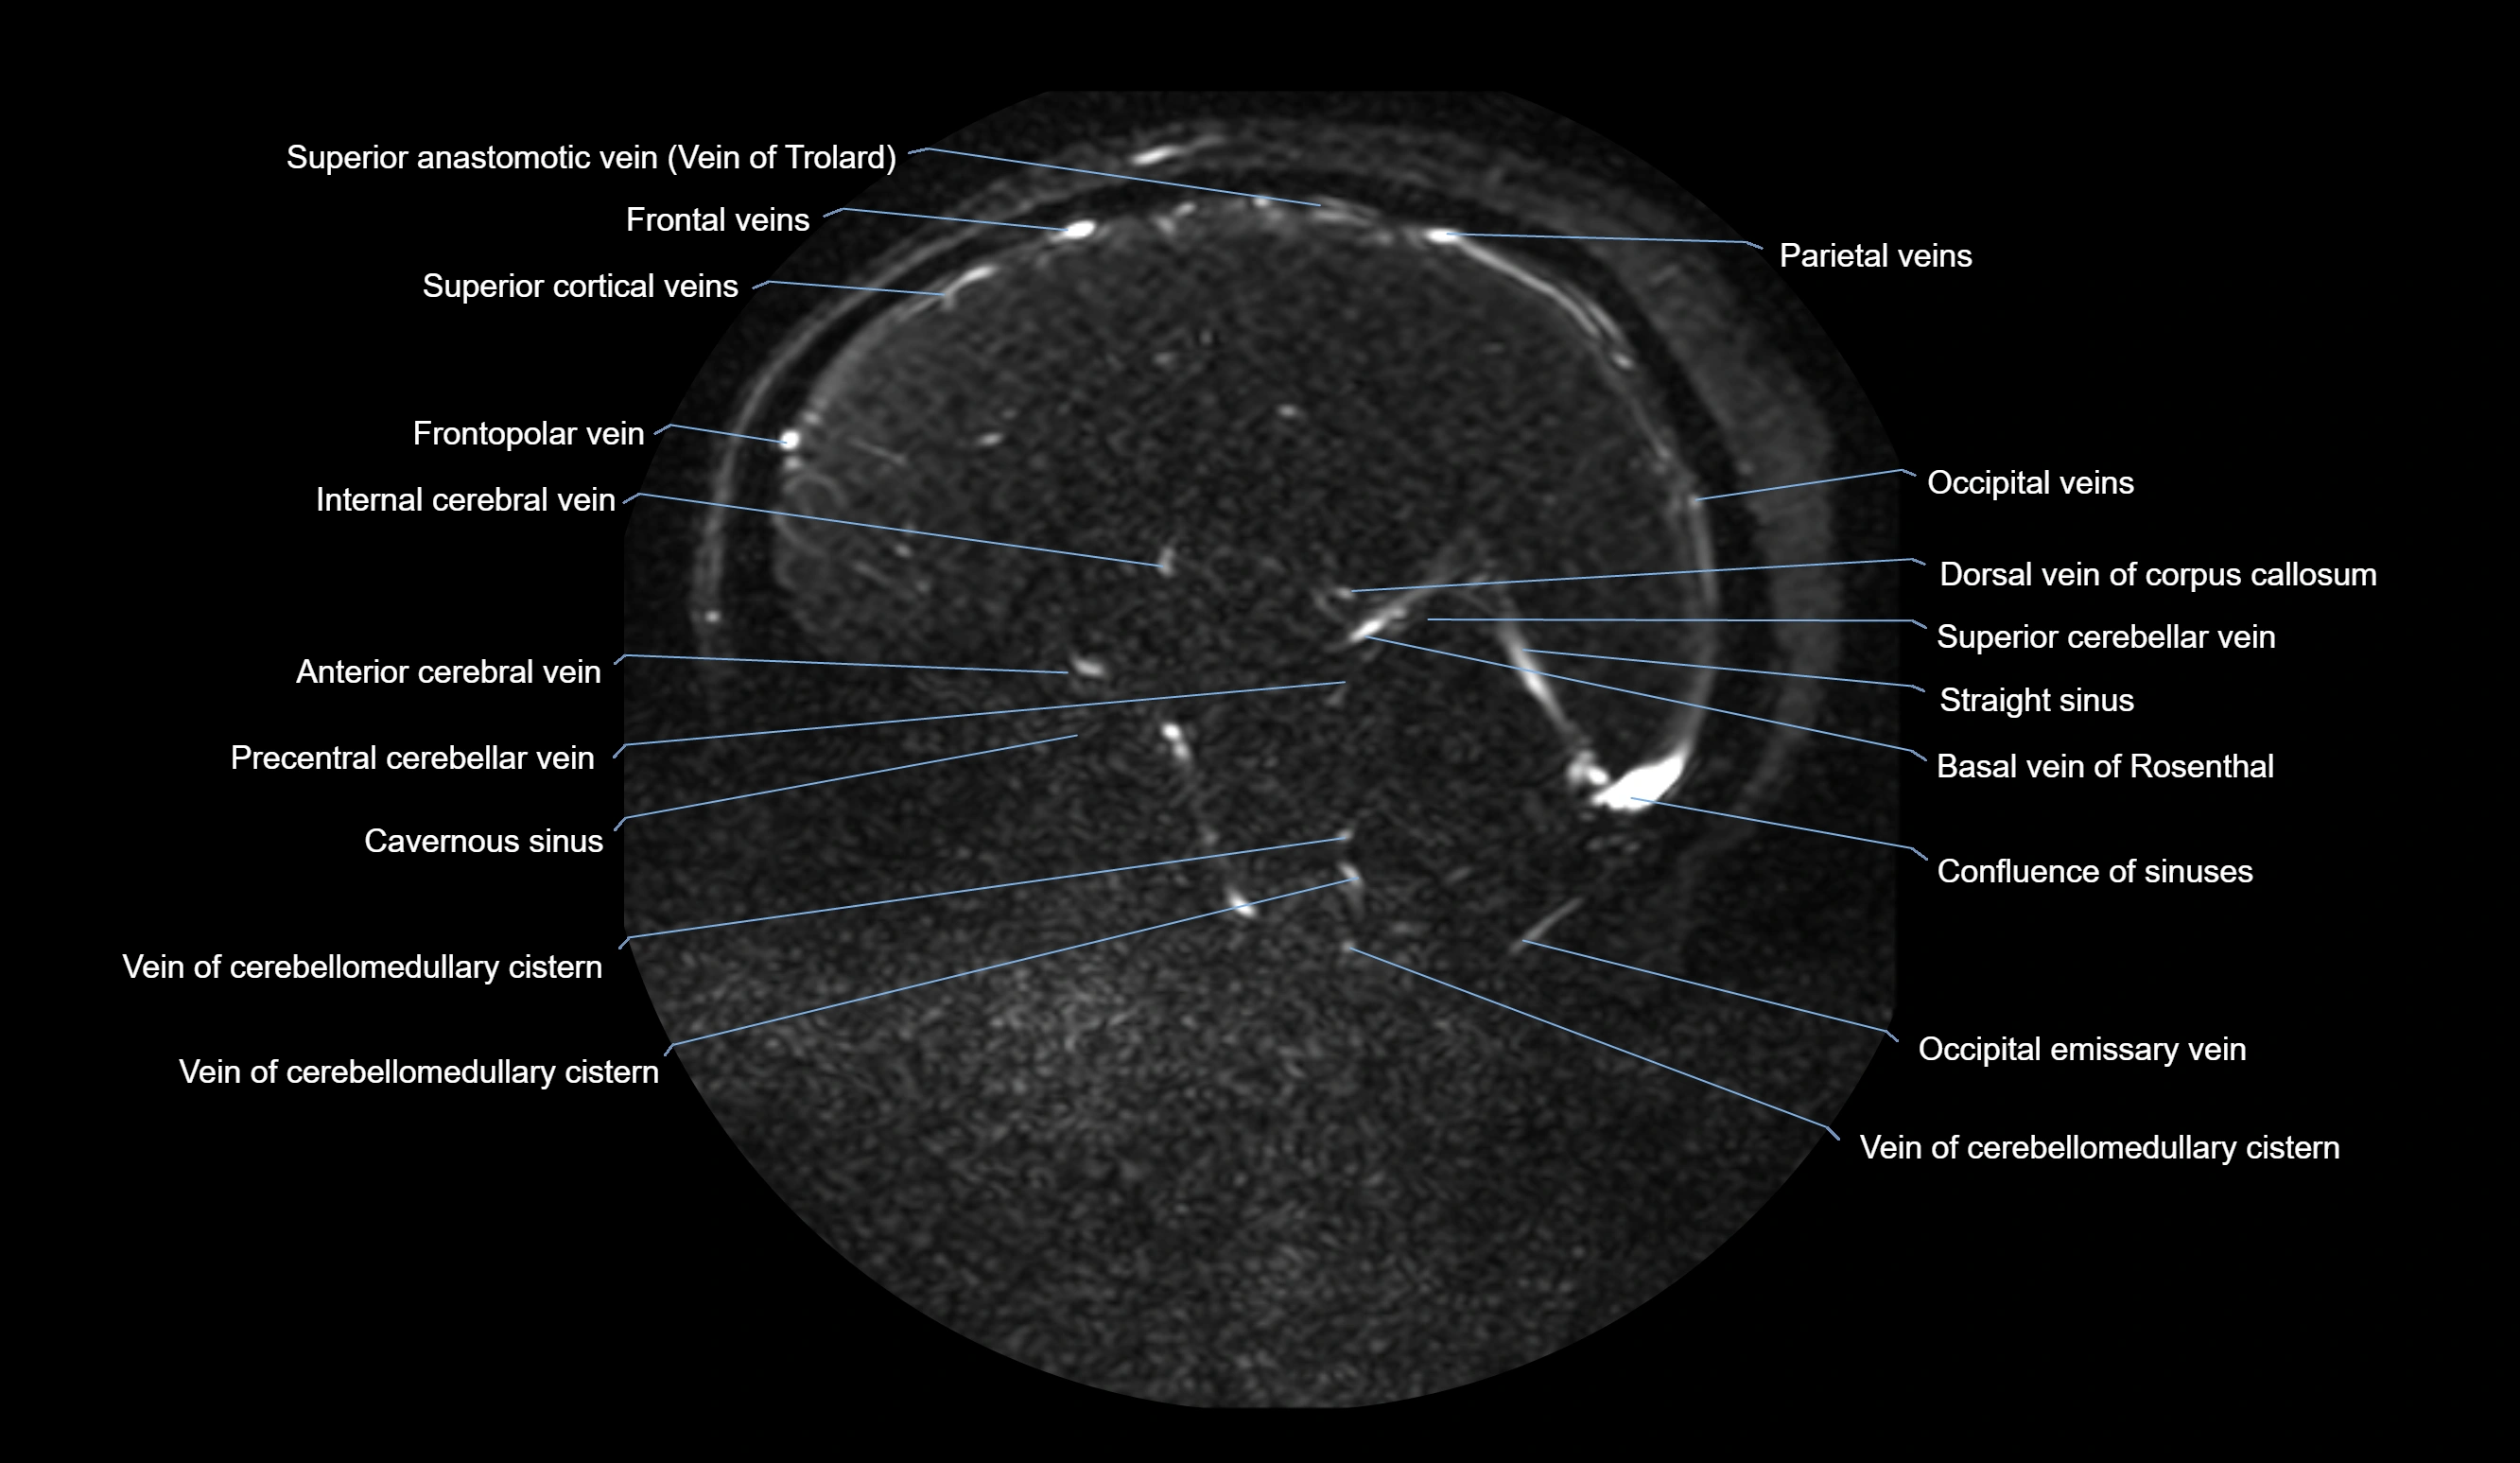

MR Venography (MRV):

• Time-of-flight (TOF) or contrast-enhanced MRV shows the angular vein as a bright enhancing venous channel

• Clearly demonstrates its continuity with the facial vein and superior ophthalmic vein

• MRV is highly useful in evaluating thrombosis, venous obstruction, or collateral venous drainage